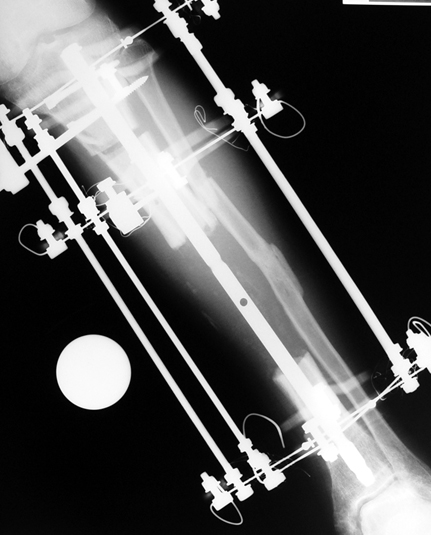

Appropriate radical debridement necessitates excision of all necrotic bone and soft tissues, and frequently causes instability at the involved extremity. The remaining bone and soft tissue defect has to be fixed and reconstructed. The distraction osteogenesis method of Ilizarov is used successfully for achievement of union, correction of the deformity, elimination of limb length inequality and reconstruction of segmental bone defects.

The duration of external fixation (external fixation index) depends on the amount of distraction required, and the extremity is prone to complications during this period. After the distraction phase is completed, the external fixator remains in place during the consolidation phase, which lasts twice as long as the distraction phase; but this period is hardly tolerated. If the external fixator is removed before sufficient consolidation is achieved, fractures, deformity and shortness will be the result. In our department, ‘lenghthening over nail’ method is used in order to decrease the external fixation index and increase patient comfort and activity level. In this method, the intramedullary nail is statically locked after the completion of the distraction phase, and external fixator is removed. The extremity is stabilized by the intramedullary nail during consolidation phase. In this way, complications due to long external fixation index or early removal of the external fixator are avoided.

Case 3